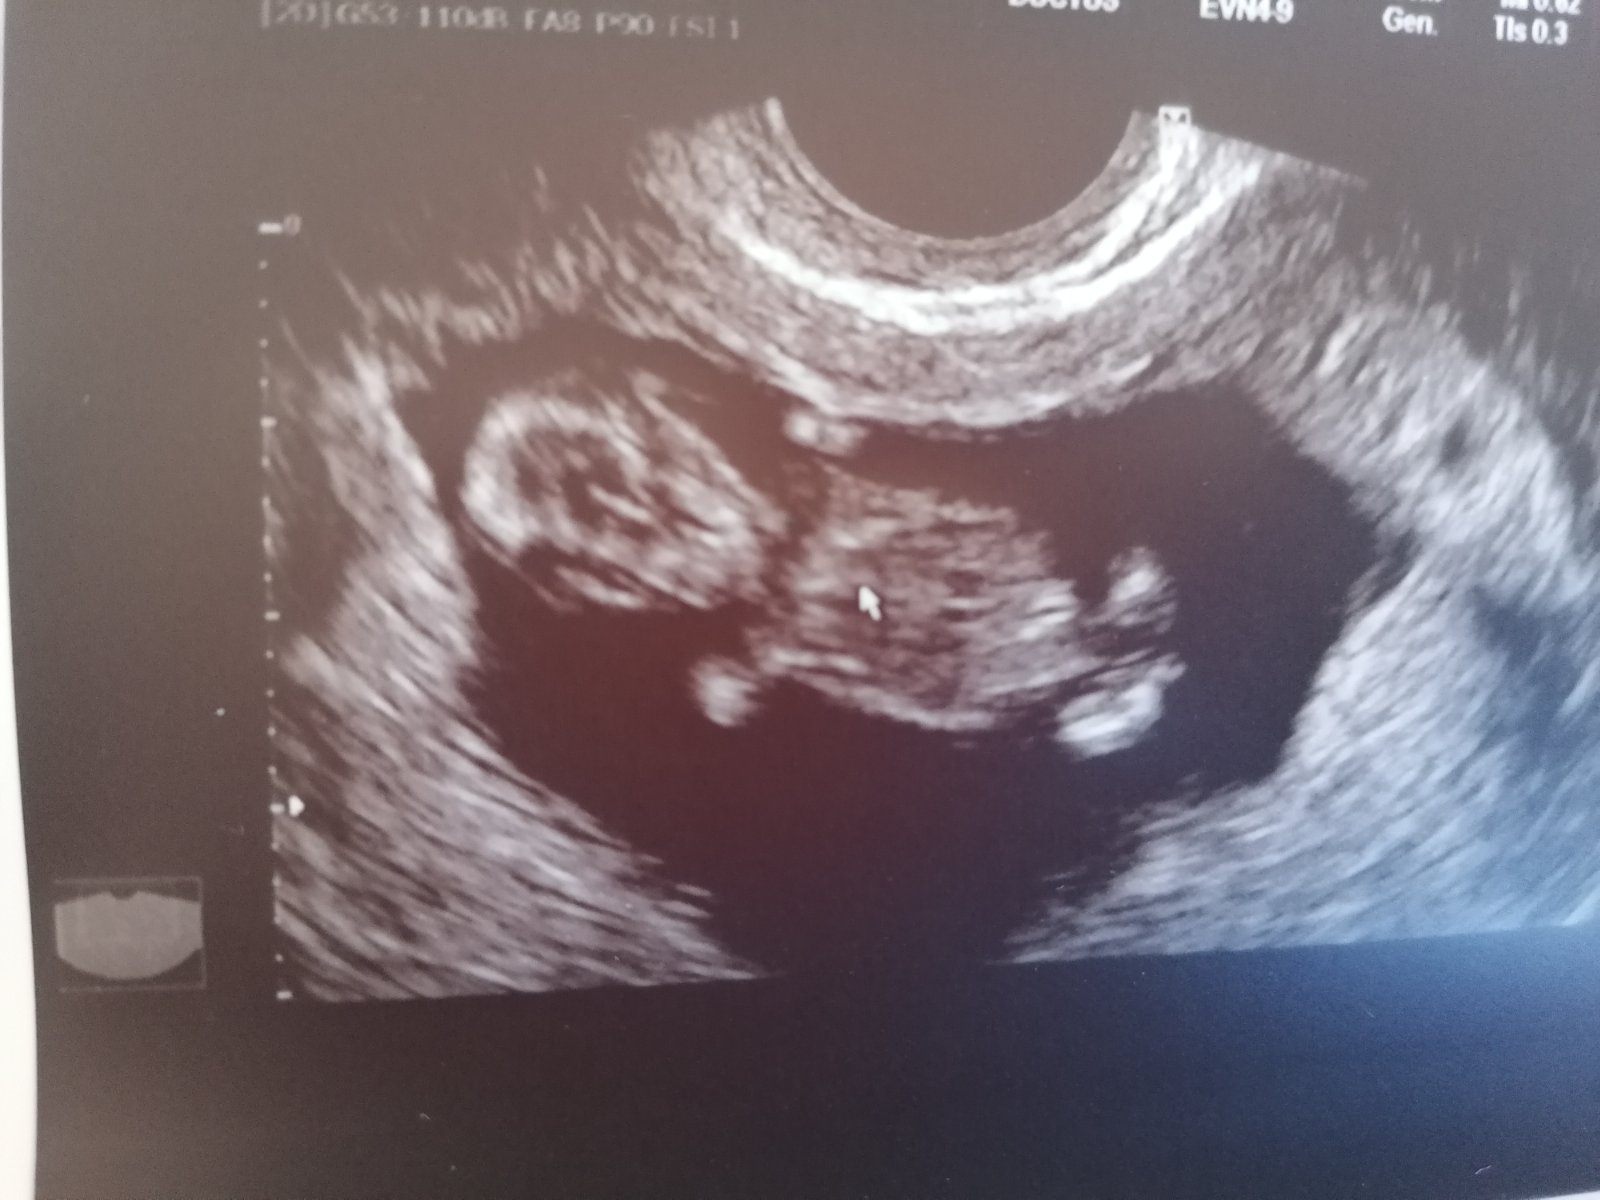

24. máj 2021

Ahojte 🥰 Plakala som od šťastia 🍀 že náš poklad, náš Magnumko je na správnom mieste v dutine v maternici 🙏 videli sme gestacny vak, žlté teliesko a embryjko 😍😍😍 na budúci týždeň ideme pozrieť akciu srdiečka ❤️ a pre knižku 🤰🍀🙏 dnes sme v 6tt 💞

Ahojte 🥰🥰 Hlásime sa z poradne ❤️ máme rúčky, nôžky a hlavičku ako ufonik ❤️❤️ 🙏🙏 stále tomu nemôžem uveriť 🤷‍♀️ taká som šťastná ale aj v strachu 😏 ten hematom ktorý tam bol, tam stále je a dokonca rastie 😒😬 mám byť v prísnom kľudovom režime viac ako doteraz 😐 no ale tešíme sa feeest a veríme, že bude všetko v poriadku 🙏🙏 🤰

Je to nádherný pocit, že vo mne rastie nový život 🤰, naše vytúžené, vybojované, vymodlené 🙏❤️ milujeme ho, náš Magnum ❤️🍀🙏 dnes 11+1 tt 🙏